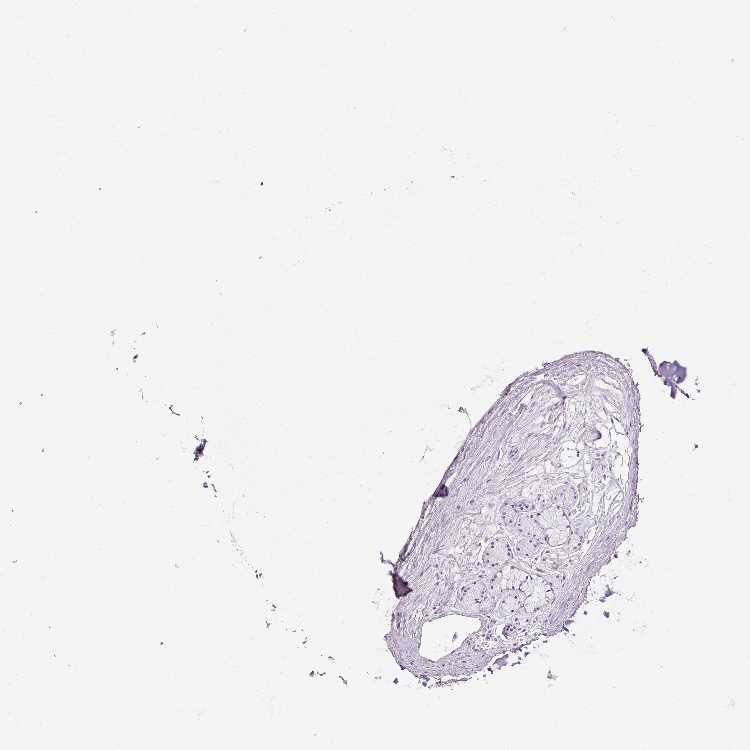

SOFT TISSUE 1 - Antibody stainingi

Antibody staining in the annotated cell types in the current human tissue is reported as not detected, low, medium, or high, based on conventional immunohistochemistry profiling in selected tissues. This score is based on the combination of the staining intensity and fraction of stained cells.

Each image is clickable and will lead to virtual microscopy that enables deeper exploration of all samples and also displays staining intensity scores, fraction scores and subcellular localization as well as patient and tissue information for each sample.

Antibody HPA047894Antibody HPA048334

Fibroblasts Not detectedNot detected

SOFT TISSUE 2 - Antibody stainingi

Peripheral nerve Not detectedNot detected